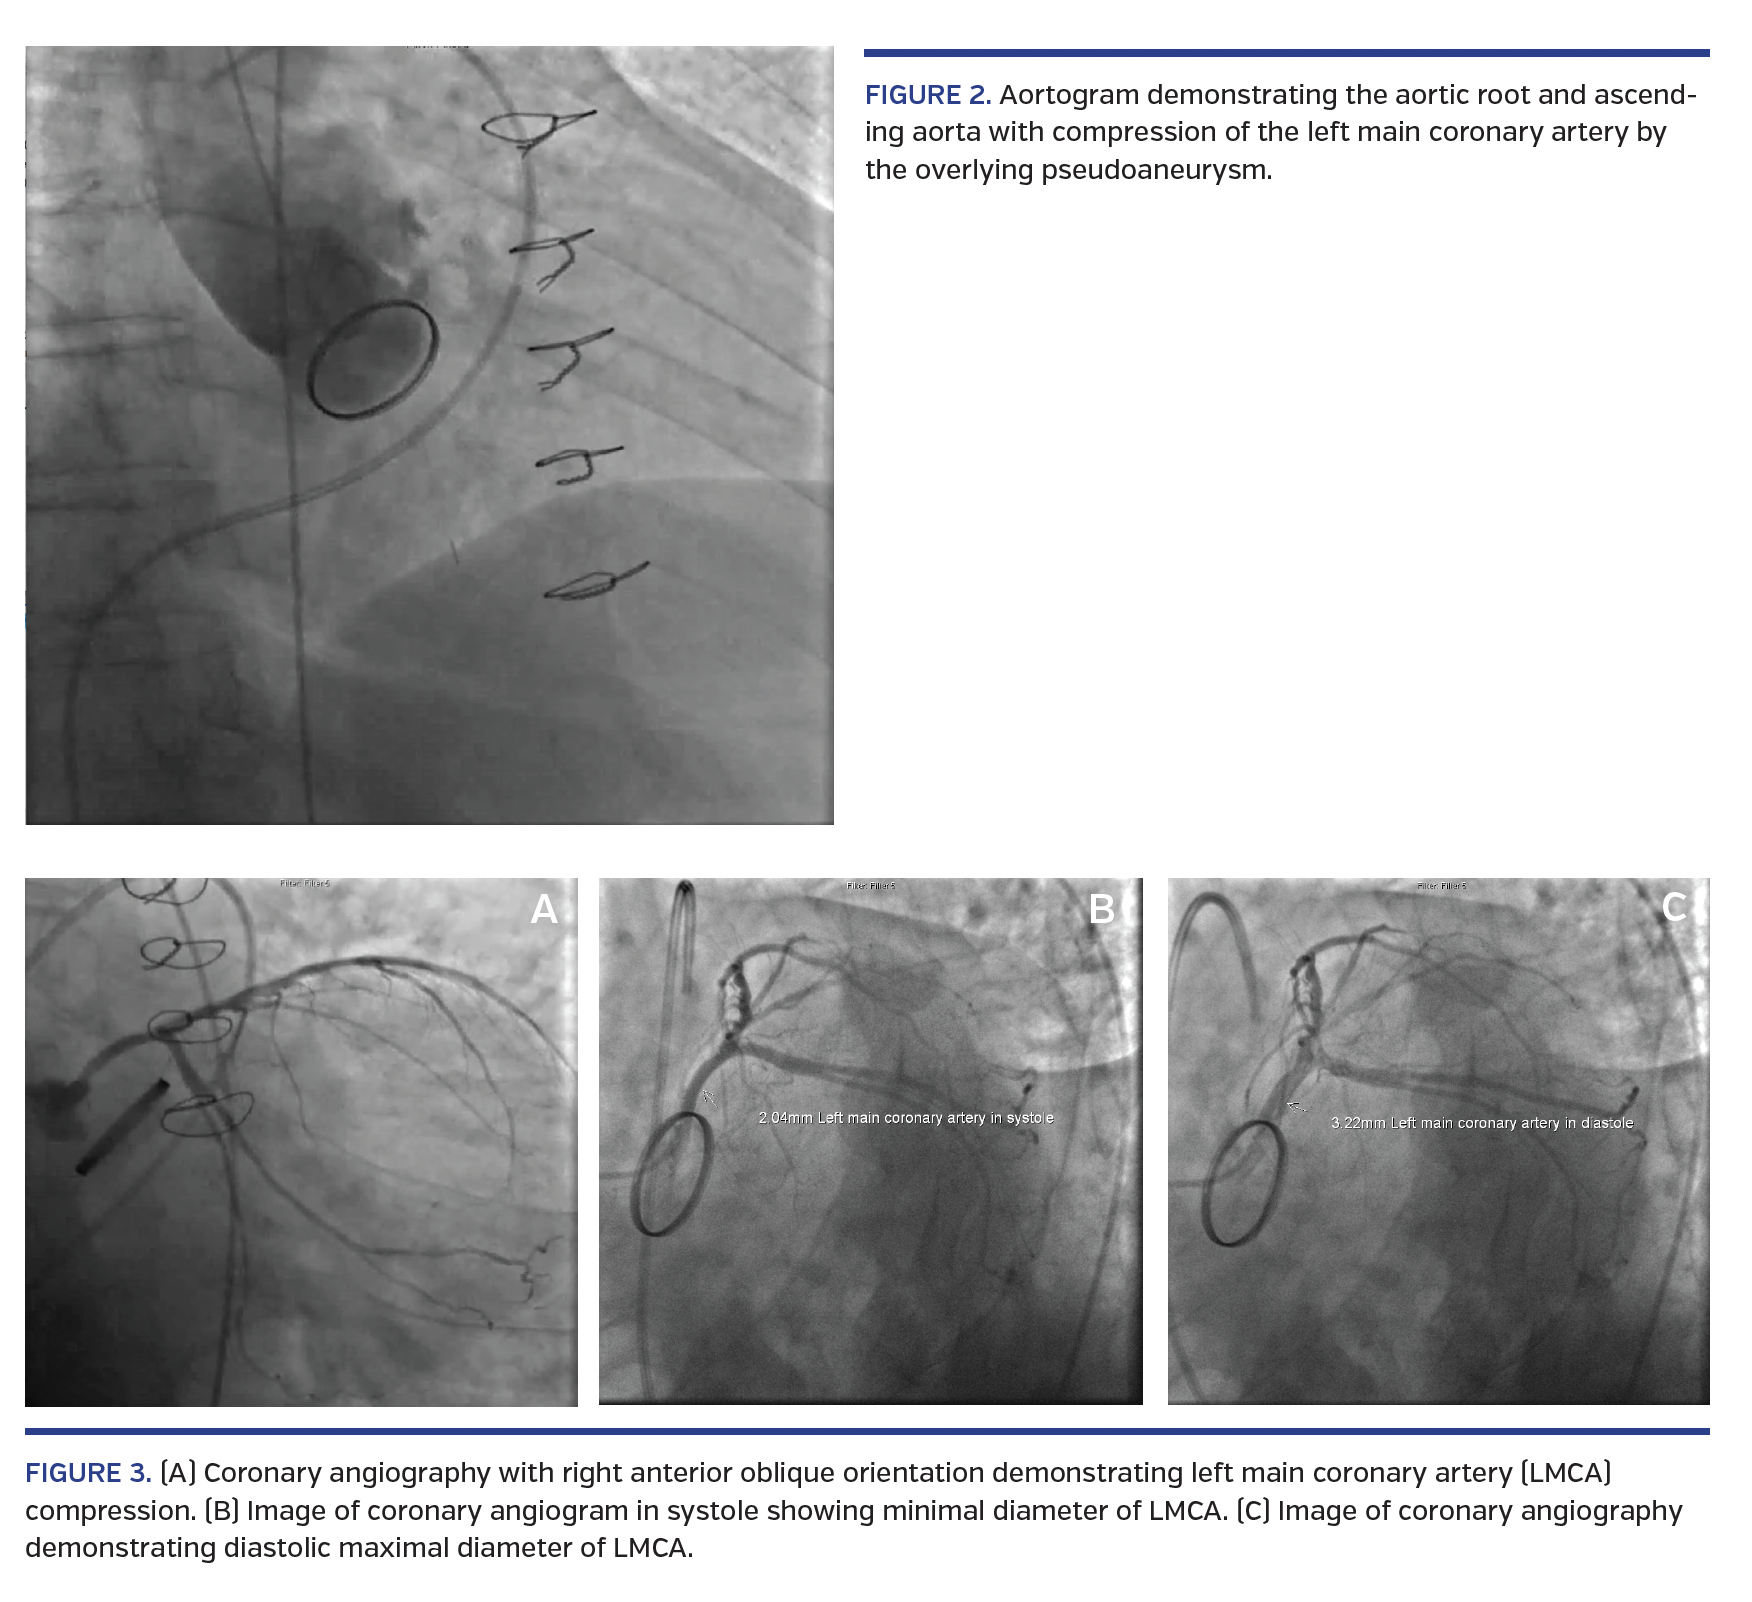

A 75-year-old man with a history of mechanical aortic valve replacement (AVR) with aortic conduit for severe aortic insufficiency underwent routine computed tomography (CT) evaluation revealing right coronary anastomosis endoleak and proximal aortic root pseudoaneurysm. The aortic dilation had been identified after the index surgery and was serially monitored. However, the follow-up CT scan revealed accelerated dilation with a 0.5 cm enlargement in 6 months. CT chest revealed close proximity of the aortic pseudoaneurysm with the ostium of the left main coronary artery (LMCA) resulting in intermittent compression (Figures 1A and 1B). Transthoracic echocardiography (TTE) revealed flow within an outpouching surrounding the proximal aortic root consistent with pseudoaneurysm. Pre-repair coronary angiography showed intermittent compression of the LMCA (Figures 2 and 3; Videos 1 and 2). The patient subsequently underwent bioprosthetic aortic valve repair with aortic conduit and re-implantation of the right and left coronary arteries due to dehiscence of the mechanical aortic valve (Figures 1C and 1D). Postoperative angiography demonstrated resolution of the aortic pseudoaneurysm and the associated LMCA compression.